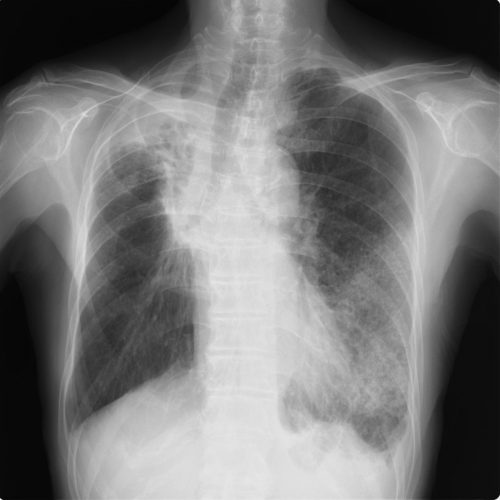

![[51]](https://www.otadragon.jp/cms/wp-content/uploads/2021/11/imageoutcrp_2-500x406.jpg)

CRP 25.1mg/dl WBC 32,500 SPO2 98%→入院紹介